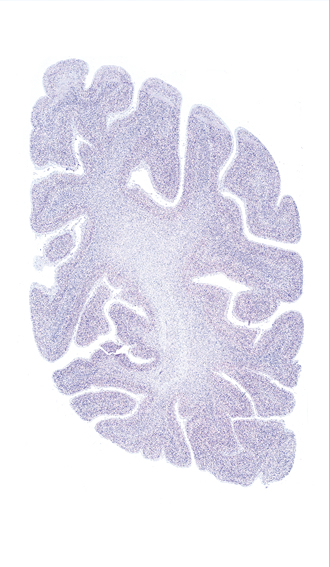

Hi-Resolution Sections · Cells (Nissl Staining) · Virtual Microscopy

Frontal sections (Nissl) from the Atlas Brain:

Slice ID:

r4-0820

Plate NR:

58

Position:

58,9 mm